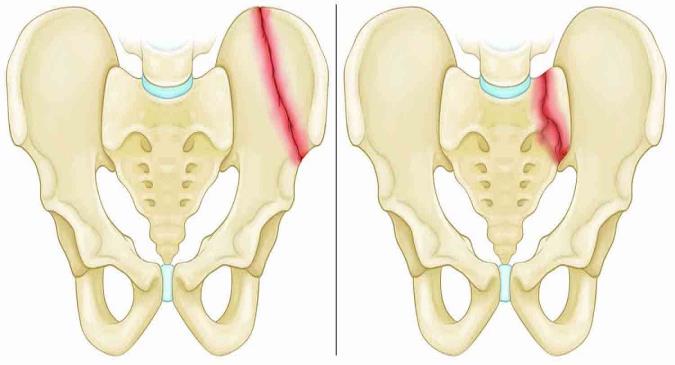

انواع شکستگیهای لگن

از آنجایی که لگن ساختاری حلقوی شکل دارد، هنگامی که آسیبدیدگی در بخشی از لگن به وجود میآید، اغلب شکستگی در نقطه مقابل آن نیز به وجود میآید. چندین الگوی شایع شکستگی لگن با توجه به جهت و شدت جراحت وجود دارد.شکستگیهای پایدار و ناپایدار

شاید مهمترین روش برای دستهبندی شکستگیهای لگن، تقسیم شکستگیها به دو نوع پایدار یا ناپایدار باشد. بیشتر شکستگیهای لگن پایدار هستند.شکستگی پایدار

استخوانهای شکسته همچنان در یک راستا قرار دارند و حلقهی لگن نیز شکل خود را حفظ داشته است. این شکستگی، تنها روی یک استخوان تاثیر میگذارد.شکستگی ناپایدار

این شکستگی معمولا زمانی رخ میدهد که دو یا چند شکستگی در حلقهی لگن وجود دارد و انتهای استخوانهای شکسته از هم جدا شده باشند. این نوع شکستگی احتمالا بعد از آسیبدیدگیهایی با تاثیر بالا و همچنین جراحات مرتبط دیگر به وجود میآیند.در این صدمات به این دلیل که در این صدمات جدا شدن استخوانها امکان خونریزی آزادانهتری را فراهم میکند، خونریزی نسبت به شکستگیهای پایدار بیشتر است. این نوع شکستگی ممکن است که موجب آسیبهای مستقیم به اندامهای داخلی نیز شود.